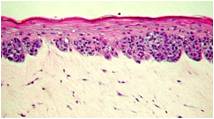

The MLNM-FT-A375 model consists of human malignant melanoma cells (A375), normal, human-derived epidermal keratinocytes (NHEK) and normal, human-derived dermal fibroblasts (NHDF) which have been cultured to form a multilayered, highly differentiated epidermis with melanoma cells at various stages of CM malignancy. At different stages of the culture, the tissue exhibits radial growth phase (RGP), vertical growth phase (VGP), or metastatic melanoma phenotype. The cells are cultured on cell culture inserts using serum free medium, and attain levels of differentiation on the cutting edge of in vitro skin technology. Structurally, the MLNM-FT-A375 model closely parallels the progression of melanoma in vivo, thus providing a valuable tool to study, understand, and develop preventative and therapeutic treatments for one of the most serious cutaneous malignancies. For more information on the Melanoma model, click here.